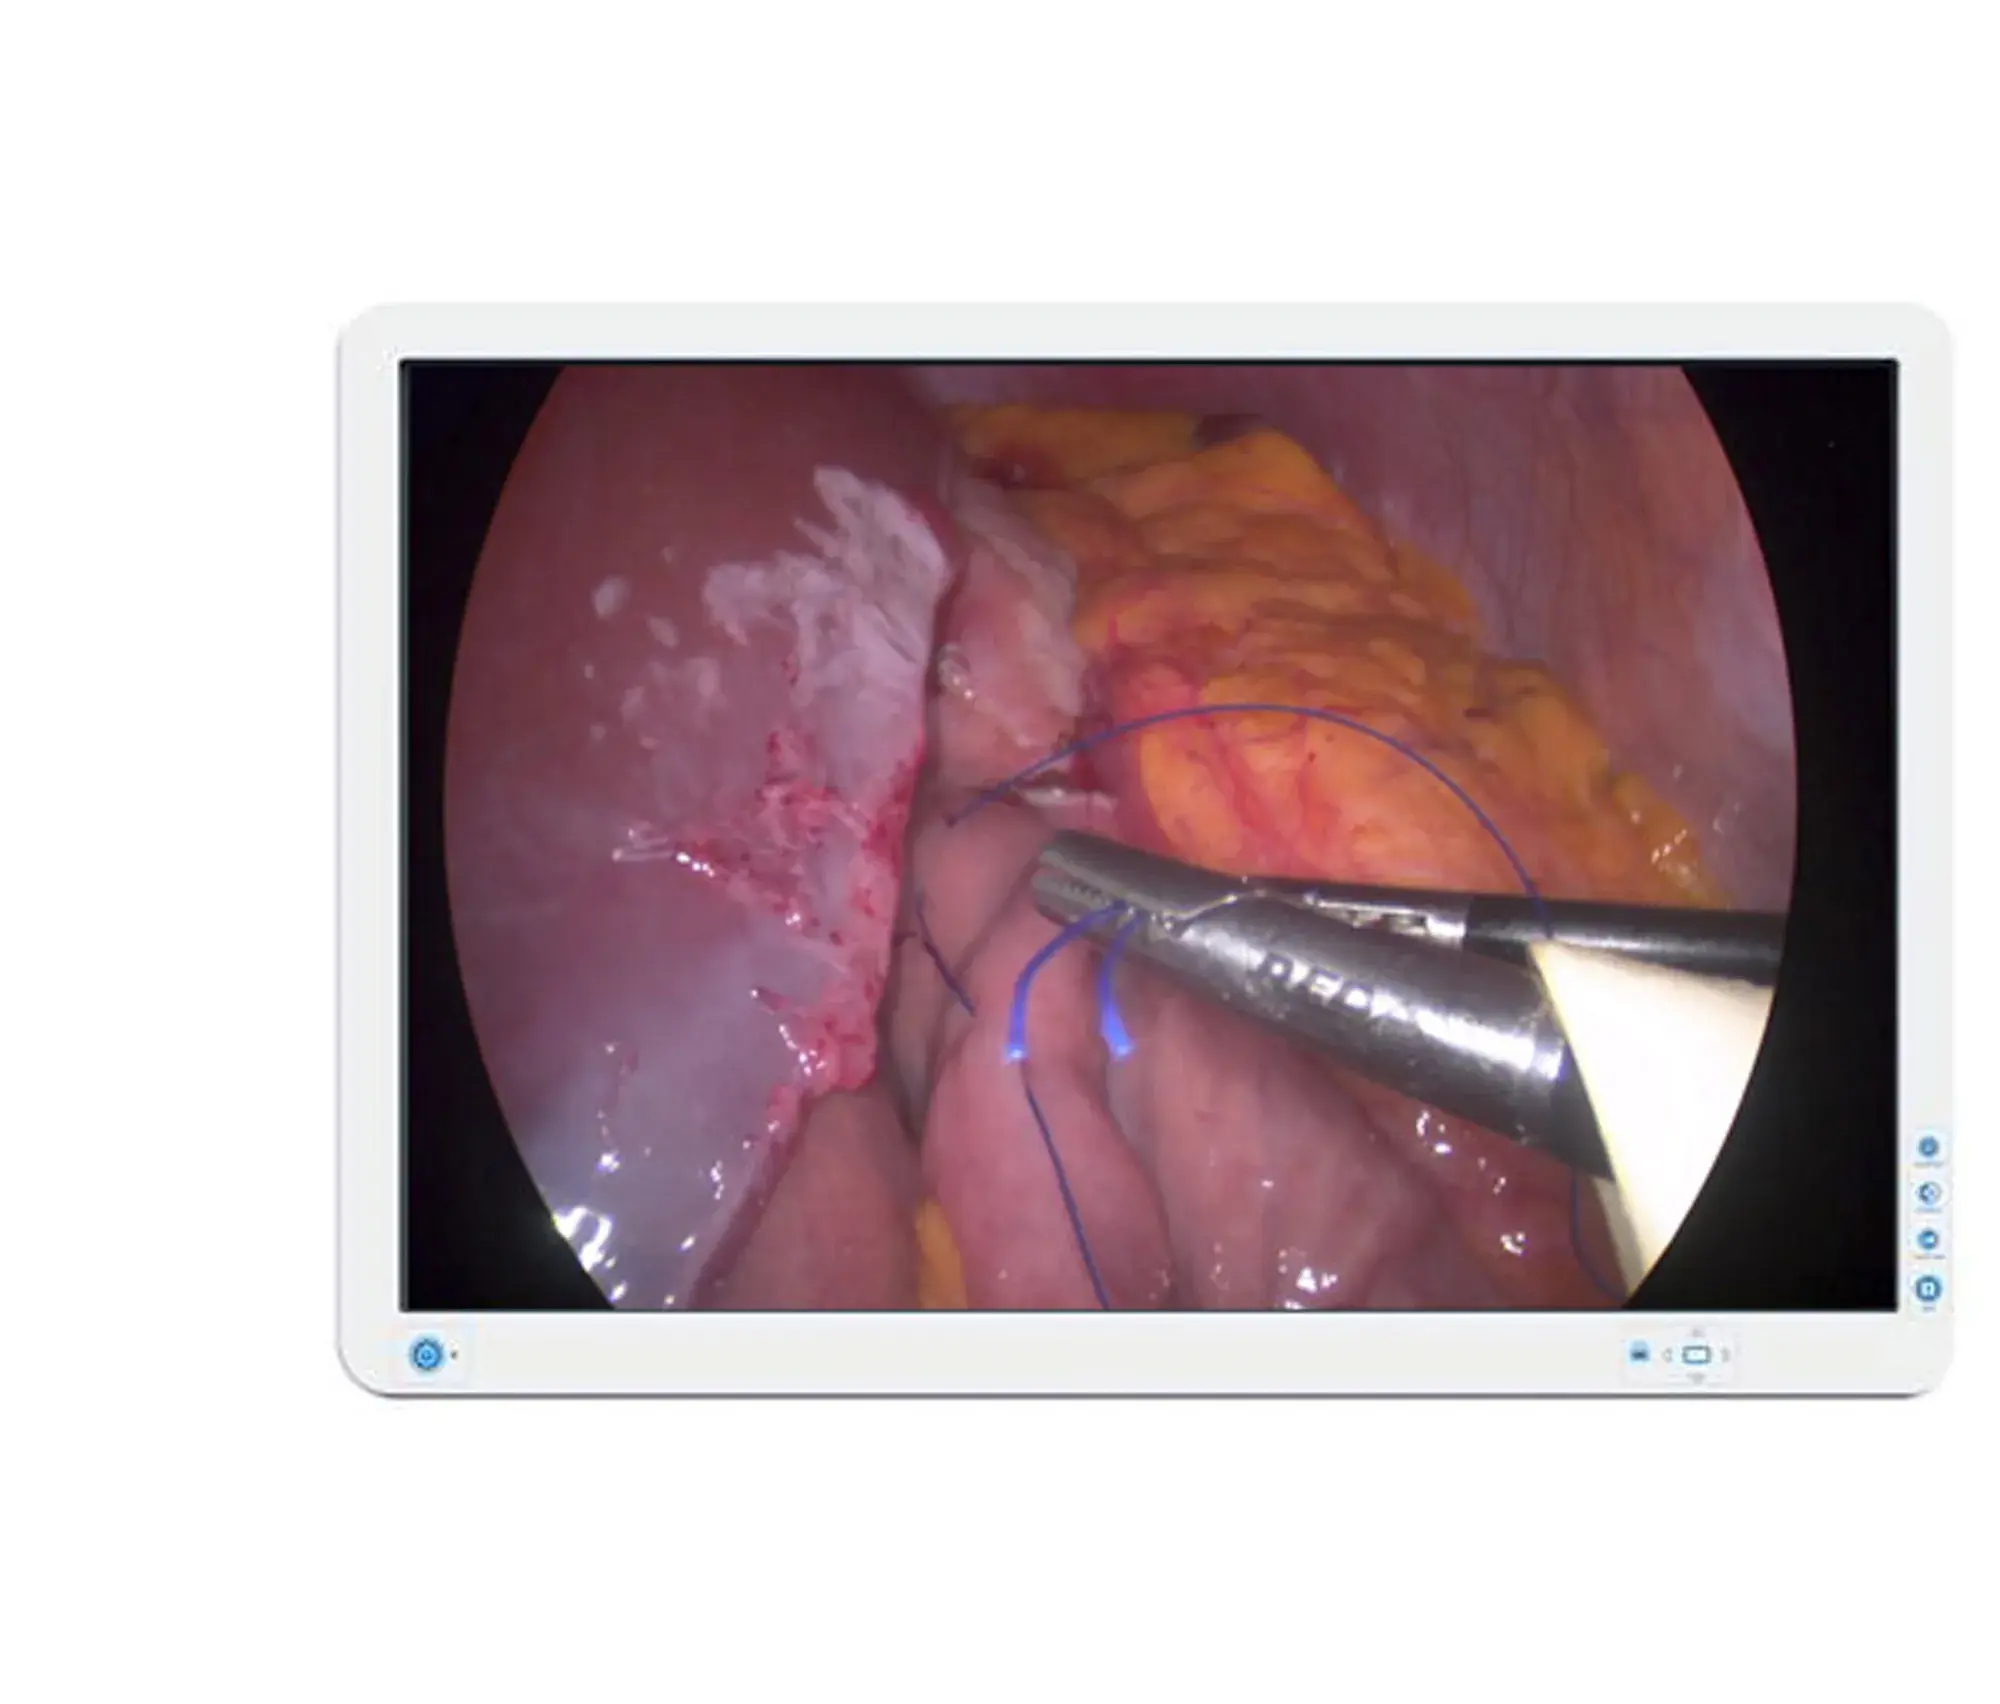

„Barco“ AMM240ED yra 24 colių chirurginis ekranas, skirtas darbui šalia paciento, su LED foniniu apšvietimu ir 1920 x 1200 skiriamąja geba. Specialiai endoskopiniams vaizdams sukurtas AMM240ED yra ekonomiškas, bet itin patikimas ekranas. Chirurginius vaizdo įrašus ir vaizdus galima rodyti „Picture by Picture“ režimu su nepriklausomais nustatymais.

Dėl sandarios konstrukcijos (IP22 apsaugos klasė), apsauginio filtro ir kabelio dangtelio AMM240ED yra saugus naudoti šalia pacientų. Jis taip pat užtikrina saugų ir lengvą montavimą ant chirurginių rankų dėl VESA atitikties.